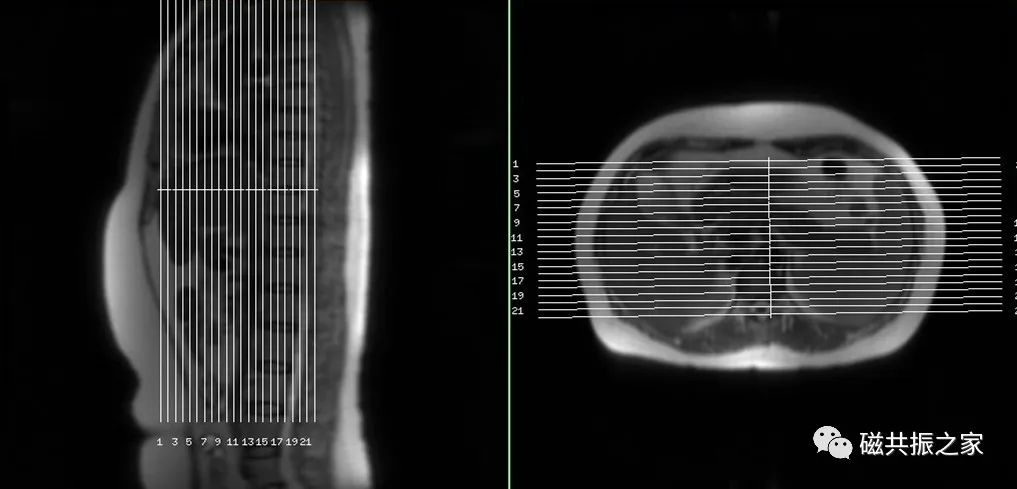

冠状面:冠状面稳态自由进动序列/单次激发T2WI序列。

在横轴位和矢状位定位,扫描范围包括肝脏前后缘,合理调整扫描范围,需包括整个病变范围。

上腹部的扫描应首先扫描范围较大的冠状面图像,以便对病变及周围组织器官作出大体地评估,更有利于精准地定位和扫描方案的制定。

横轴面:横轴面T2WI脂肪抑制序列

在矢状位和冠状位上定位。扫描范围上至肝顶,下至十二指肠,合理调整扫描范围,需包括整个病变范围。